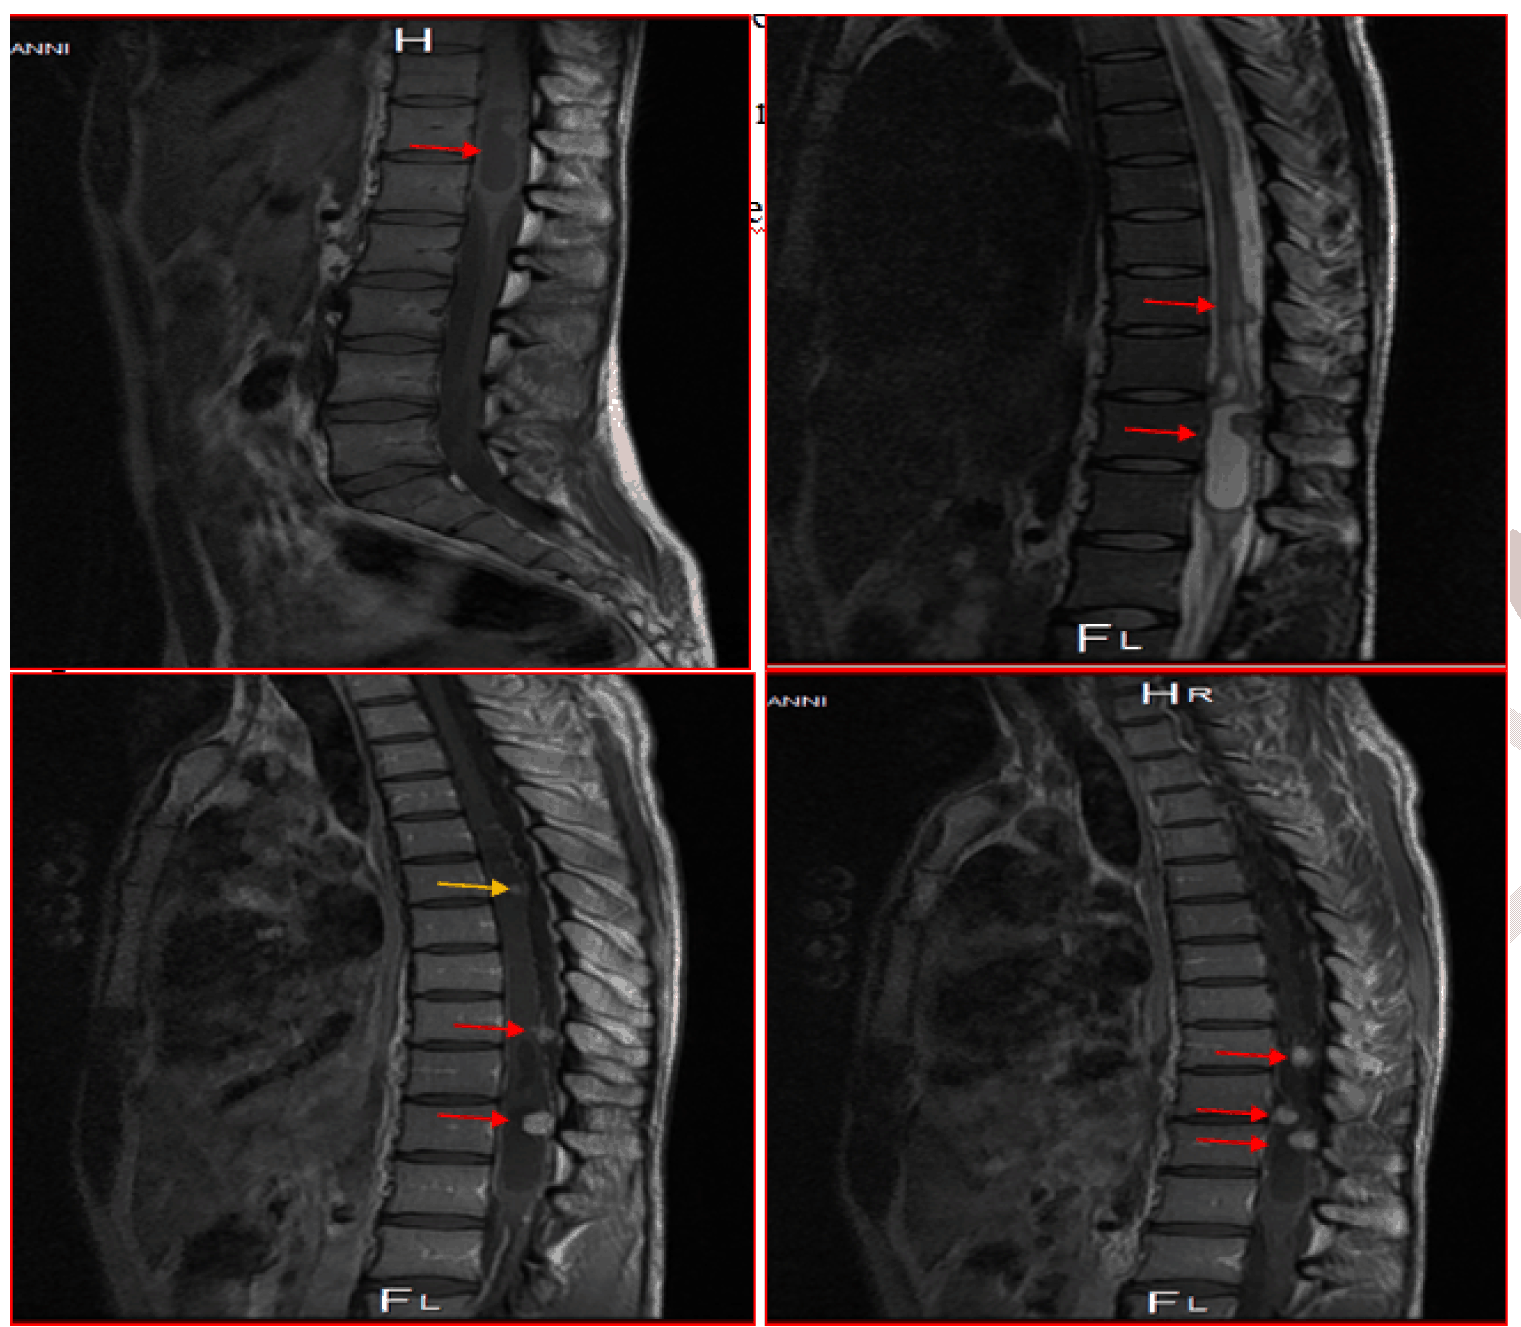

An MRI of the spine showed multiple intramedullary masses. The symptomatic lesions was situated in the terminal cone; the largest mass measured 48×13×1O mm in size. The mass appeared as a cystic lesion with a tissural mural nodule, with hypointense T1 inhomogeneous signal, with increased gadolinium uptake in T1, with perilesional oedema. Just above this mass, there are two other small cystic lesions, up to 1/3 medium of the vertebral body T6; one of the nodules had a subdural extra axial component (Figure 1) and (Figure 2).

Figure 1: Magnetic resonance imaging scan of the spine showing multiple intramedullary masses. The symptomatic lesions was situated in the terminal cone (red arrow); the largest mass measured 48×13×10 mm in size. The mass appeared as a cystic lesion with a tissural mural nodule, with hypointense T1 inhomogeneous signal, with increased gadolinium uptake in T1.

Figure 2: Magnetic resonance imaging scan of the spine (axial) showing the three symptomatic intramedullary masses was situated in the terminal cone.